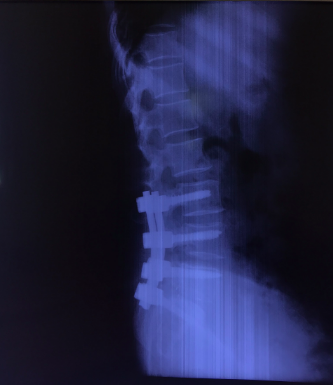

Sau khi hội chẩn, bệnh nhân được chỉ đỉnh phẫu thuật cố định cột sống và hàn xương liên thân đốt lối sau qua lỗ liên hợp (TLIF). 4 ngày sau phẫu thuật, bệnh nhân đã có thể ngồi dậy, tập đi lại trong khung tập đi, triệu chứng lâm sàng đã giảm đi rõ rệt: không còn cảm giác đau lan dọc 2 chân, cảm giác 2 chân trở nên nhẹ nhàng hơn, chỉ còn đau nhẹ vết mổ.

Hình ảnh: X Quang bệnh nhân sau phẫu thuật hàn xương, nắn chỉnh cột sống